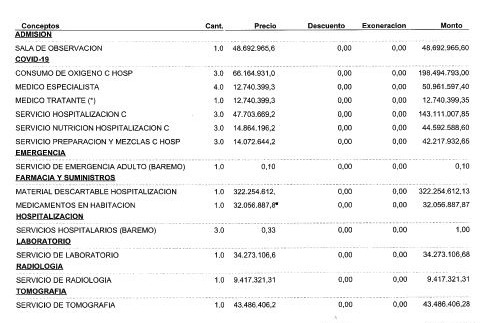

Con los cuidados intensivos, los costos se incrementan considerablemente. A los 3.600 dólares iniciales por la hospitalización se suman otros 10.000 dólares más las medicinas y demás cuidados que necesita (adjuntos los informes y presupuestos).

With intensive care, the costs increase considerably. To the initial $3,600 for the hospitalization is added another $10,000 plus the medicines and other care he needs (reports and estimates attached).

Con los cuidados intensivos, los costos se incrementan considerablemente. A los 3.600 dólares iniciales por la hospitalización se suman otros 10.000 dólares más las medicinas y demás cuidados que necesita (adjuntos los informes y presupuestos).

With intensive care, the costs increase considerably. To the initial $3,600 for the hospitalization is added another $10,000 plus the medicines and other care he needs (reports and estimates attached).